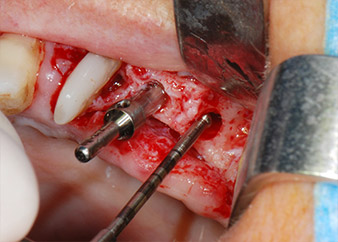

Sinus lift and implant placement

Prior to implant placement, infected tissue was removed from the alveolar bone in the implant site and around the abutment teeth with an insert originally designed for bone shaping and collecting bone chips (Piezomed, insert B5) (Figs. 6 and 7).

piezo-electric scraping instrument

Fig. 6: The surgical site was debrided with a piezo-electric scraping instrument designed for collecting bone particles and modeling bone.

osseous defects

Fig. 7: After cleaning the osseous defects mesial to tooth 27 and around the root of tooth 24 were clearly visible.